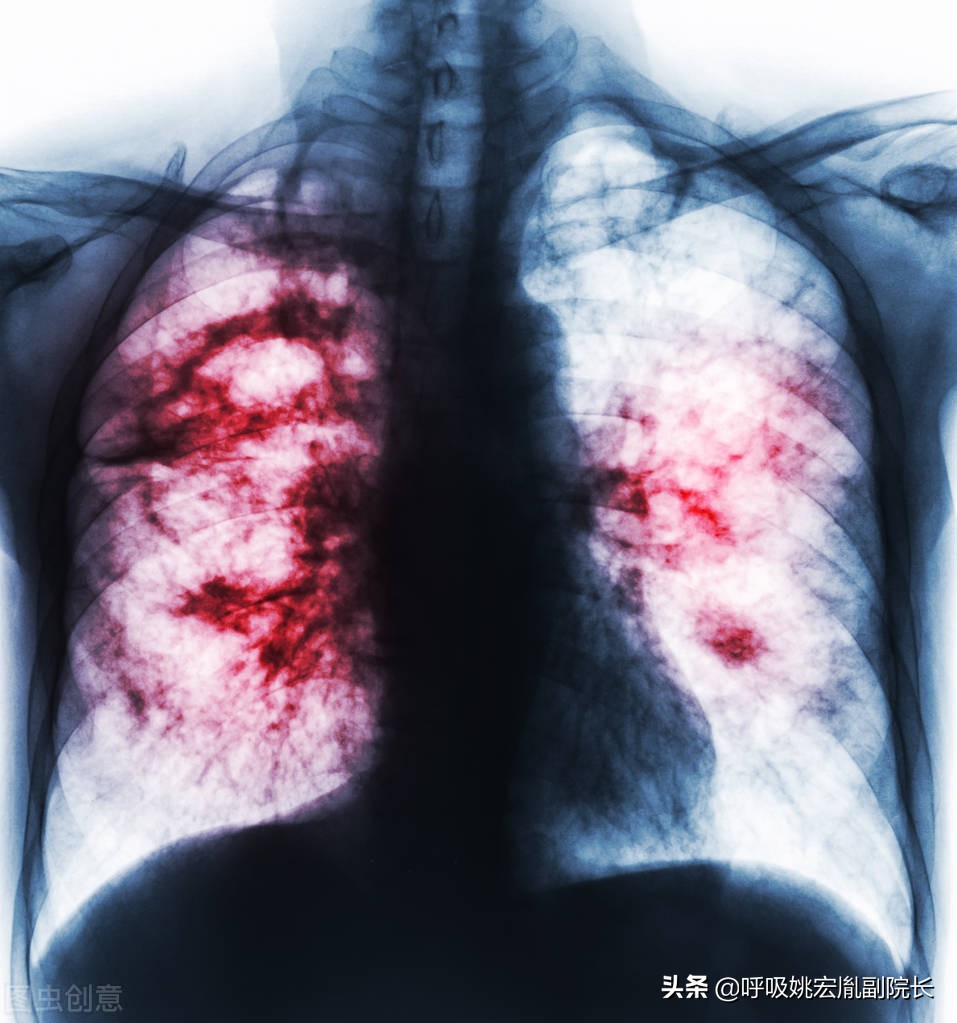

肺炎:

老年肺炎常缺乏明显呼吸系症状,症状多不典型,病情进展快,易发生漏诊、错诊。首发症状为呼吸急促及呼吸困难,或有意识障碍、嗜睡、脱水、食欲减退等。